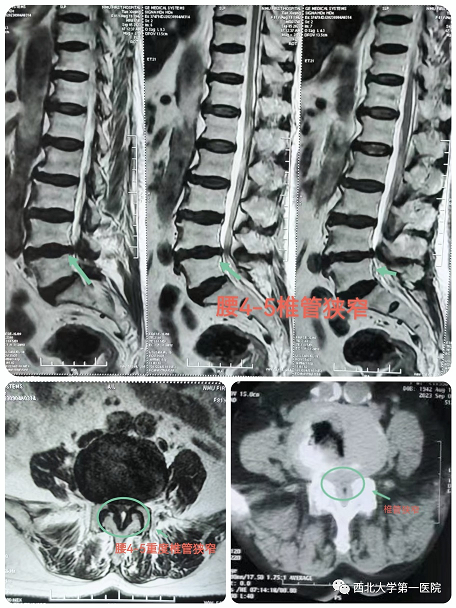

患者田某某,女,81岁,有腰腿痛病史10余年,近期出现左下肢放射痛,不能长距离行走,辗转多家医院保守治疗,效果不佳,行走困难,严重影响日常生活和休息,为求诊治,来我院骨科三病区。啪啪啦 脊柱外科团队经过细致的体格检查及辅助检查,明确诊断:腰4-5椎管狭窄症。患者症状体征与检查结果相符,重度椎管狭窄,继续保守治疗可能没有效果。患者高龄,81岁,基础病较多,开放手术风险较高,患者及家属不能接受,与患者及家属充分沟通后,建议可以考虑微创椎管减压术,在取得患者家属的理解后,同意行微创手术治疗。

经过充分的术前讨论及围手术期多学科讨论评估后,决定采用目前最新脊柱内镜技术:OSE(Open Spine Endoscope)单孔脊柱内镜技术,行腰4-5椎管狭窄单侧入路、双侧减压、脊神经根粘连松解术。手术切口约2cm,术中出血10ml左右,由于不破坏关节突关节,不影响脊柱稳定性。术后第二天患者佩戴腰带下地活动,症状明显缓解,效果非常满意。

术中可见椎管减压彻底,神经根完全松解